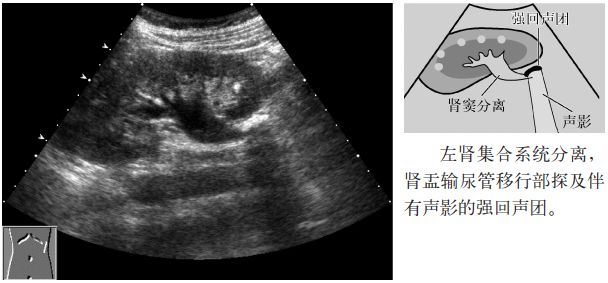

图2 肾结石

2.伴有中心部回声(central echoes,central echo complex,CEC;肾窦)分离(肾积水)。

图10 输尿管结石(肾盂输尿管移行部)